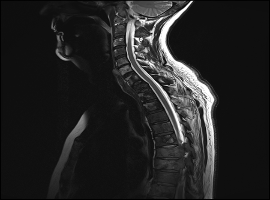

A Case-Matched Study Comparing Surgery to No Surgery in Patients with Metastatic Spinal Cord Compression

Background: Patients with MSCC present with pain and/or neurological loss. NICE guidance recommends surgery to prevent paralysis or manage pain in paralysed patients. There is only one RCT comparing surgery with no surgery, which strongly recommends surgery, however, there have been advances in radiotherapy with better local control and lower normal tissue toxicity.